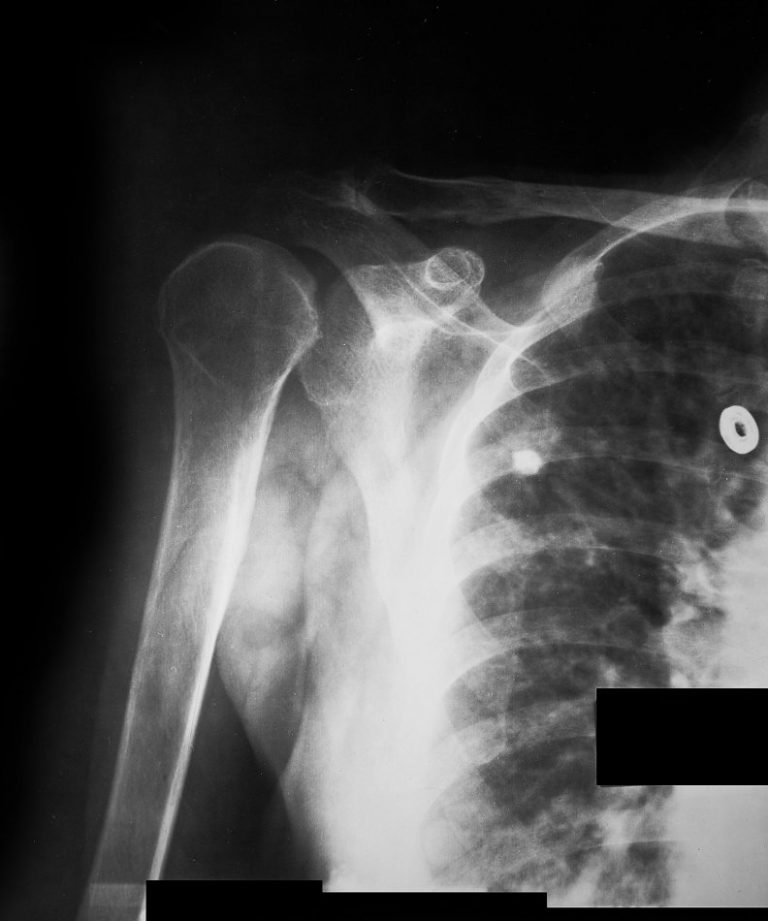

Normal Shoulder Joint X Ray

What Does A Normal Shoulder X Ray Look Like Ideally, a shoulder radiograph series will provide adequate views of the clavicle, acromioclavicular joint (acj), glenohumeral. As you've already seen, this isn't the. A normal shoulder x ray will demonstrate the bones of the shoulder to have expected normal appearance without breaks,. Ideally, a shoulder radiograph series will provide adequate views of the clavicle, acromioclavicular joint (acj), glenohumeral. A video tutorial in interpreting radiographs of the shoulder joint and surrounding areas.